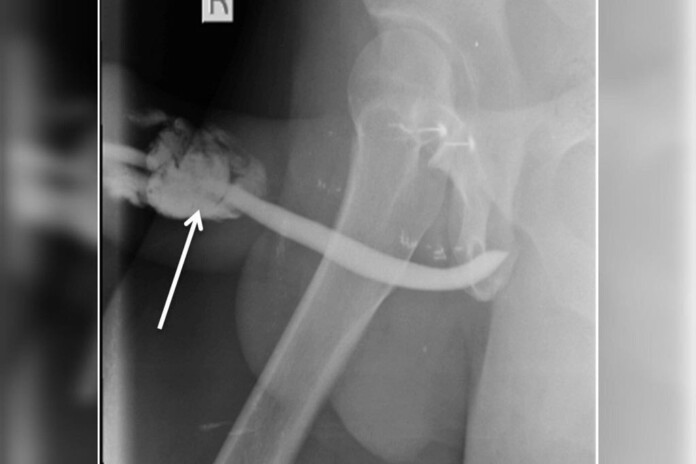

Um homem teve uma rara fratura em três lugares diferentes do pênis durante o sexo. O caso ocorreu com um morador da Tanzania de 36 anos enquanto ele fazia uma das posições sexuais mais propensas a ocorrerem lesões deste tipo.